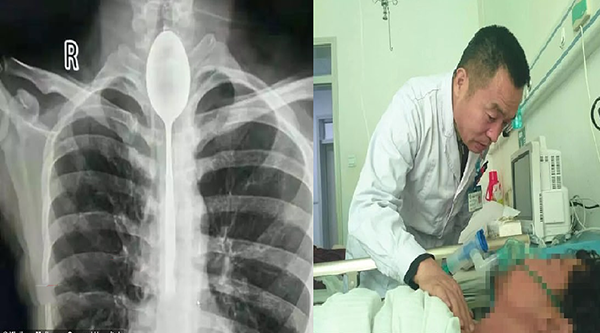

இந்த நிலையில் அவருக்கு திடீரென நெஞ்சு வலி அதிகரித்துள்ளது. உடனே மருத்துவமனையில் அனுமதிக்கப்பட்டவருக்கு மருத்துவர்கள் ஸ்கேன் செய்து பார்த்தனர். அப்போது உணவுக்குழாயில் 8 அங்குல இரும்பு கரண்டி இருப்பதை பார்த்து அதிர்ச்சிடையடைந்துள்ளனர்.

உடனே அவசரமாக அறுவை சிகிச்சைக்கு ஏற்பாடு செய்த மருத்துவர்கள், 2 மணி நேர அறுவை சிகிச்சைக்கு பின் எண்டோஸ்க்கோப்பின் உதவியுடன் கரண்டியை வெளியில் பிரித்தெடுத்தினார். இந்த சம்பவம் தொடர்பாக மருத்துவர் கூறுகையில், ஆரம்பத்தில் கரண்டியை பார்த்து நாங்கள் அனைவரும் ஆச்சர்யமடைந்தோம். தற்போது அறுவைசிகிச்சைக்கு பின்னர் அவர் நலமாக உள்ளார். இன்னும் இரண்டு நாட்களில் வீடு திரும்பிவிடுவார் என தெரிவித்துள்ளார்.